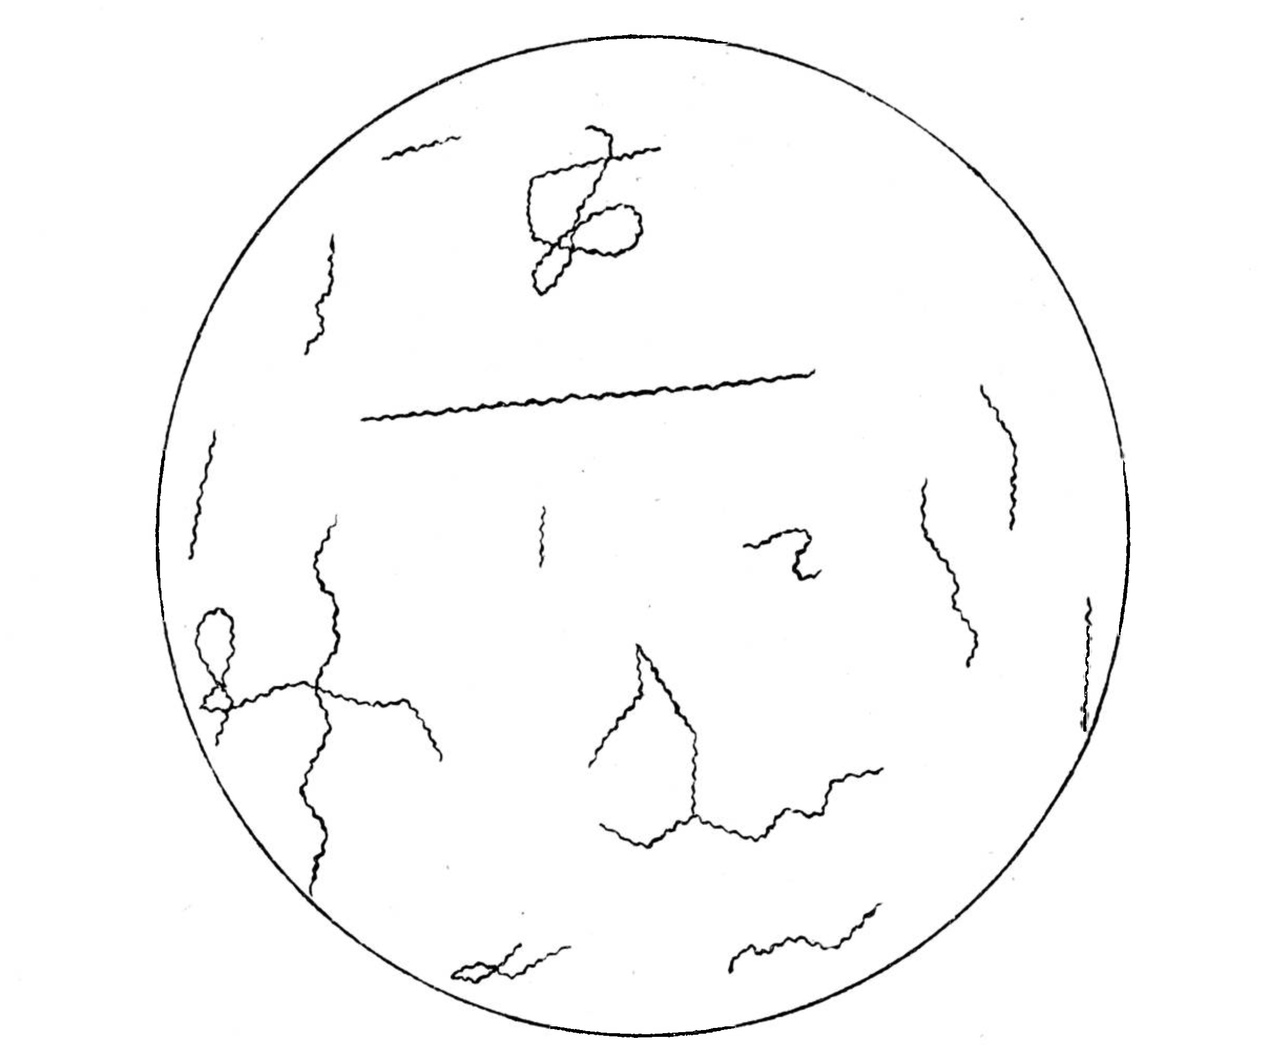

Исходя из этих соображений, я прежде всего попробовал заменить „свежую" ткань и „свежий" кровяной сгусток более индифферентным с химической точки зрения веществом—свернутым белком куриного яйца. Куриное яйцо, лишь-бы оно не обладало явными признаками порчи, варится обычным образом ввод: „вкрутую", после чего белок тщательно отделяется от желтка и делится ножом на кусочки объемом в 1-2 куб. сайт., которые распределяются по пробиркам. Белка из одного куриного яйца достаточно для заполнения 12—15 пробирок. Затем в пробирки прибавляется по 8 куб. сайт, физиологического раствора хлористого натрия; в таком виде пробирки стерилизуются в автоклаве при 120º в течение 15 минут. Остается теперь добавить всюду по 4 куб. сайт, не нагретой лошадиной сыворотки, и среда готова для посева. На приготовленной таким образом питательной среде мне удалось получить с первого же раза очень богатую культуру спирох Obermeiera. Достаточно посеять 1—2 капли крови больного, чтобы через несколько дней при температуре 37°C. получить богатую культуру,—когда при рассматривании капли питательной среды пот микроскопом в поле зрения видно 30—40 спирохет, а иногда и больше. Генерации полученных из крови человека спирохет удаются легко, и в настоящее время я имею в лаборатории 19-ю генерацию первого штамма, выкультивированного из крови больного два месяца тому назад. Развитие культуры идет быстрее, чем это описывают Nogouchi и Hata. Обычно maximum роста достигается па 4—5 день. В культуре можно видеть формы спирохет, отличающиеся по длине и взаимному расположению: наряду с очень короткими спирохетами встречаются экземпляры, по крайней мере в 10 раз превышающие их по длине; большею частью спирохеты располагаются отдельно одна от другой, но вместе с тем можно видеть и аггломерати спирохет, состоящие из 5—6 особей, образующих очень красивые фигуры звезд с расходящимися в разные стороны лучами; иногда можно бывает отметить, как две спирохеты, большею частью длинные, перевиваются, переплетаются одна вокруг другой подлиннику; встречаются, наконец, фигуры, которые проще всего трактовать, как явление поперечного деления спирохет, и которые характеризуются тем, что две спирохеты, большею настаю короткие и находящиеся в оживленном движении, соединены между собою тоненьким, едва заметным мостиком, имеющим вид очень нежной нити. Нужно отметить, что в зависимости от периода развития спирохет в культуре преобладают те или другие формы. Длинные спирохеты, звездообразные фигуры и перевивающиеся формы появляются в культуре в первые дни роста: наоборот, для периода maximum'a роста является характерным как- бы наводнение культуры мелкими формами спирохет, прядающими картине однообразный вид. (См. прилагаемые рисунки).

Приложение к статье В. М. Аристовского.

По культировании спирохеты Obermeier’a“ Культура спирохеты Obermeier’a на среде с куриным белком.

Рис. 3. 3-х суточная культура.

Рис. 4. 4-х суточная культура.